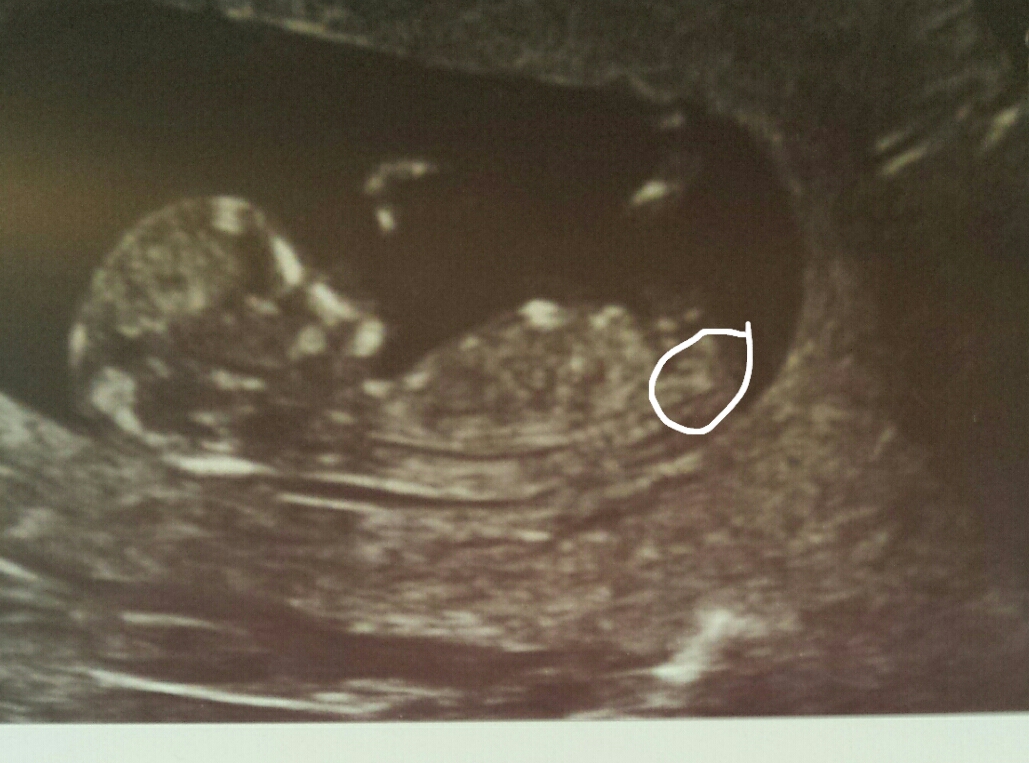

Attachment 26074Attachment 26073

Not confident I see gender clues

Looks like a boy :)

boy!

Leaning girl.. not seeing an angle.

boy lean xx

Here is another pic of same scan, I have circled what I think is the nub? Or am I getting it completely wrong? x

Thats more the spine area, the nub is right at the top of that area :) I would guess boy foy you also but there is alot of jumble going on!

Leaning boy

Boy lean